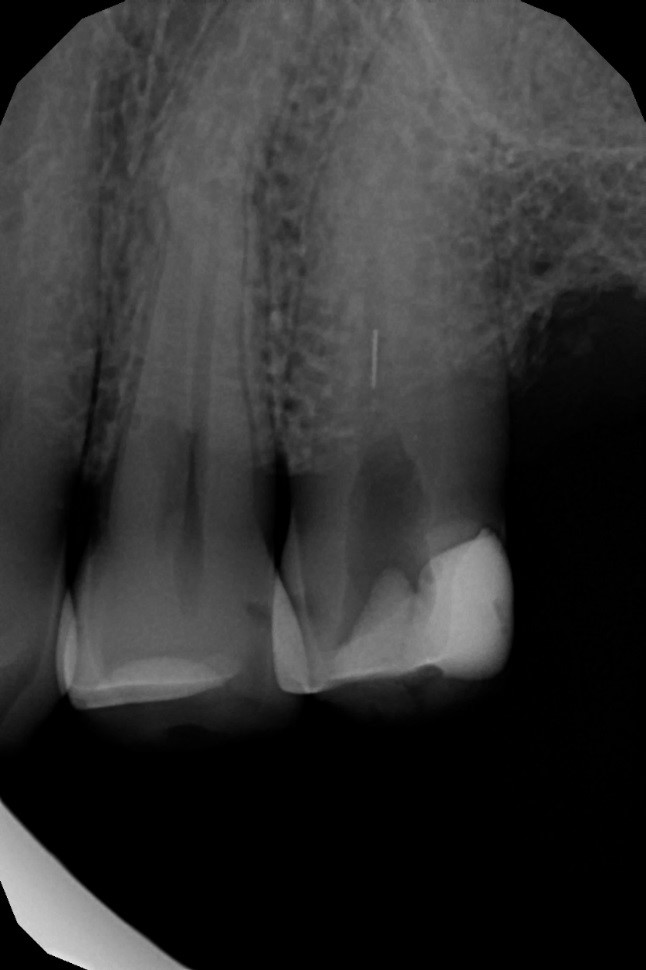

IV. Złamane narzędzie kanałowe

Złamane narzędzia są jednym z powikłań, które mogą wystąpić podczas leczenia kanałowego. Dzięki zastosowaniu odpowiedniego instrumentarium można jednak w wielu przypadkach usunąć złamany fragment narzędzia z kanału i doprowadzić do ostatecznego sukcesu terapii endodontycznej (ryc. 12‑14). Gdy narzędzia nie uda się usunąć, można spróbować wykonać zabieg jego obejścia, tak zwany bypass, a następnie szczelnie wypełnić kanał korzeniowy. Podczas całej procedury opracowania należy obficie płukać kanał, najlepiej stosując również aktywację za pomocą urządzeń dźwiękowych lub ultradźwiękowych. Jeśli do złamania narzędzia doszło jakiś czas temu, kanał jest prawidłowo wypełniony, a ząb asymptomatyczny i nie wymaga nowej odbudowy, można wstrzymać się od ingerencji stomatologicznej, ale koniecznie obserwować ząb zarówno w badaniu klinicznym, jak i radiologicznym. Sam fakt obecności złamanego narzędzia w jamie zęba nie kwalifikuje go od razu do powtórnego leczenia kanałowego, a już na pewno nie do ekstrakcji.

Ryc. 12. Zdjęcie rentgenowskie zęba 25 wykonane przed podjęciem leczenia w specjalistycznej poradni endodontycznej – widoczne złamane narzędzie w kanale korzeniowym.

Źródło: Olczak K. Złamane narzędzia kanałowe – powikłanie w endodoncji, z którym można sobie poradzić. Mag Stomatol. 2019; 9: 13.

Ryc. 13. Zdjęcie rentgenowskie zęba 25 wykonane po usunięciu narzędzia.

Źródło: Olczak K. Złamane narzędzia kanałowe – powikłanie w endodoncji, z którym można sobie poradzić. Mag Stomatol. 2019; 12: 13.

Ryc. 14. Zdjęcie rentgenowskie zęba 25 wykonane po wypełnieniu kanałów korzeniowych.

Oczywiście decyzja co do przyszłości zęba ze złamanym narzędziem jest uzależniona od:

- momentu, w którym doszło do złamania narzędzia,

- jakości wypełnienia kanału,

- stanu tkanek okołowierzchołkowych,

- ogólnego zdrowia pacjenta,

- całościowego planu leczenia (25, 26).